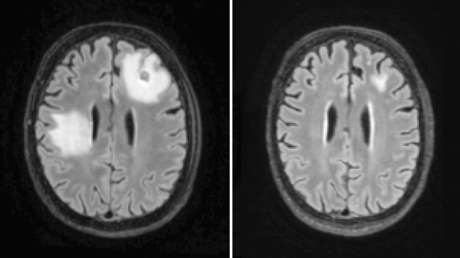

Se trata de una rara infección causada por la ameba 'Naegleria fowleri'. Las autoridades sanitarias también señalaron que los humanos pueden contraer la enfermedad solo cuando el agua contaminada con la ameba entra por la nariz, pero no al beberla.

Por ahora, la PAM no tiene ningún tratamiento efectivo. Según los CDC, la tasa de mortalidad por esta infección es de más del 97 %. De 154 pacientes registrados en Estados Unidos entre 1962 y 2021, solo cuatro han logrado sobrevivir a la afección.